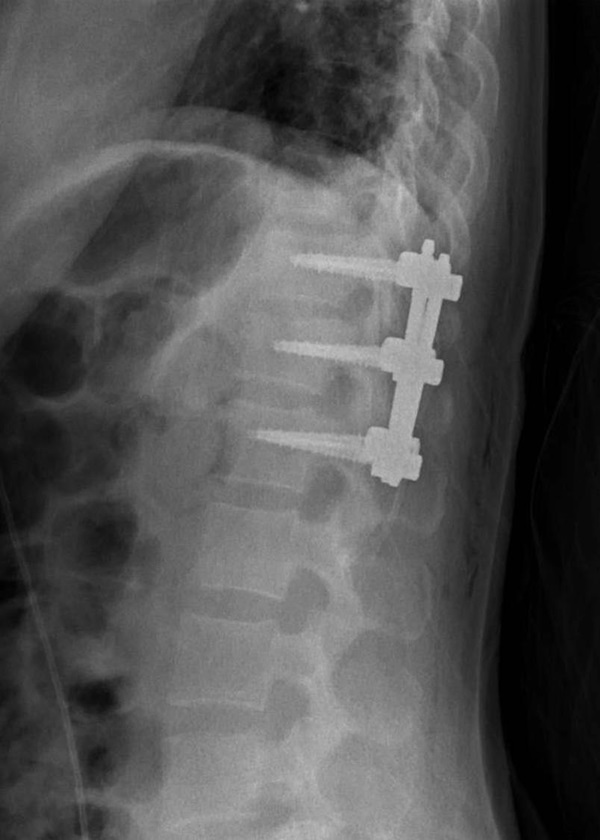

จากเหตุการณ์สุดระทึกกรณี หมอโอ๋ ผู้ช่วยศาสตราจารย์แพทย์หญิงจิราภรณ์ อรุณากูร กุมารแพทย์เวชศาสตร์วัยรุ่น โรงพยาบาลรามาธิบดีฯ และเจ้าของเพจ เลี้ยงลูกนอกบ้าน เจอประสบการณ์เฉียดตาย หลังตัวเองและครอบครัวเข้าพักรีสอร์ตสุดหรูระดับ 6 ดาว บนเกาะกูด จ.ตราด ราคาคืนละ 500,000 บาท แต่เกิดไฟไหม้อย่างรุนแรง โดยไร้สัญญาณเตือน ทำให้ตัวหมอโอ๋ต้องหนีเอาชีวิตรอด จนหล่นจากที่สูงและกระดูกสันหลังหัก และต้องทำการผ่าตัด เหตุเกิดเมื่อต้นเดือนมีนาคม 2565 นั้น

เกี่ยวกับเรื่องนี้ วันที่ 6 มิถุนายน 2565 หมอโอ๋ โพสต์ผ่านเพจ เลี้ยงลูกนอกบ้าน เล่าเรื่องราวหลังครบรอบ 3 เดือน เหตุการณ์ไฟไหม้รีสอร์ตหรู จ.ตราด ซึ่งที่ผ่านมามีคนสอบถามด้วยความห่วงใยอยู่ตลอด ตอนนี้อาการดีขึ้นพอกลับไปทำงาน ใช้ชีวิตได้ใกล้เคียงปกติ แต่ยังปวดหลังด้านล่างเมื่อต้องนั่งนาน ๆ หรือตอนขยับ ตอนกลางคืนนอนพลิกตัวก็ยังตื่นเพราะรู้สึกเจ็บ เพราะเป็นจากกล้ามเนื้อหลังด้านล่างที่เคยบาดเจ็บ ยังไม่แข็งแรงดี ซึ่งอีก 1-2 ปี อาจจะต้องผ่าตัดเอาเหล็กออก ขึ้นอยู่กับเอ็นที่ยึดกระดูกสันหลังจะติดหรือไม่ ส่วนสภาพจิตใจครอบครัวยังโอเค ยอมรับว่ามีอาการนอนสะดุ้งบ้างเมื่อไปนอนโรงแรมที่ลักษณะคล้ายกัน